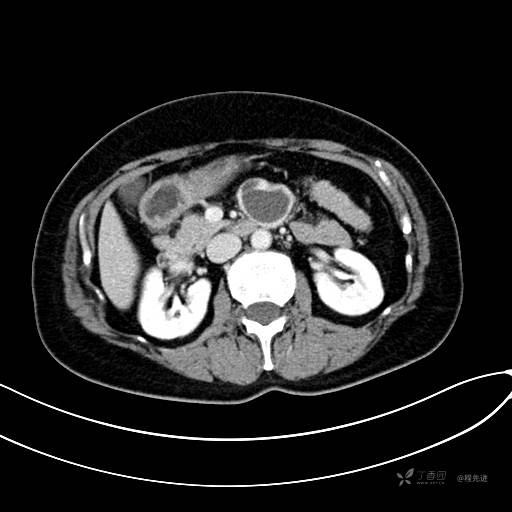

CT增强静脉期